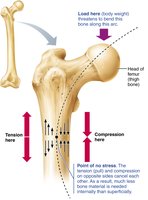

Mechanical stress: Wolff’s law states that bone grows/remodels in response to mechanical demands.